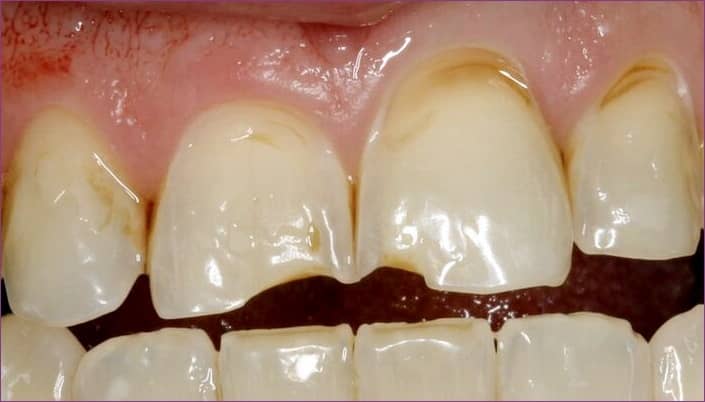

Például azzal, hogy hosszú ideig kortyolgat egy limonádét, vagy citromgerezdeket rágcsál-szopogat. A felpuhult fogzománcot ugyanis akár egy enyhe mechanikus hatás is károsíthatja, a hosszú ideig tartó vagy gyakori savas hatás pedig saverózót okozhat. A lenti képen látszik, hogy a savak pusztító munkája felemészti a fogzománcot, szélsőséges esetben a fogzománc akár teljesen eltűnhet!